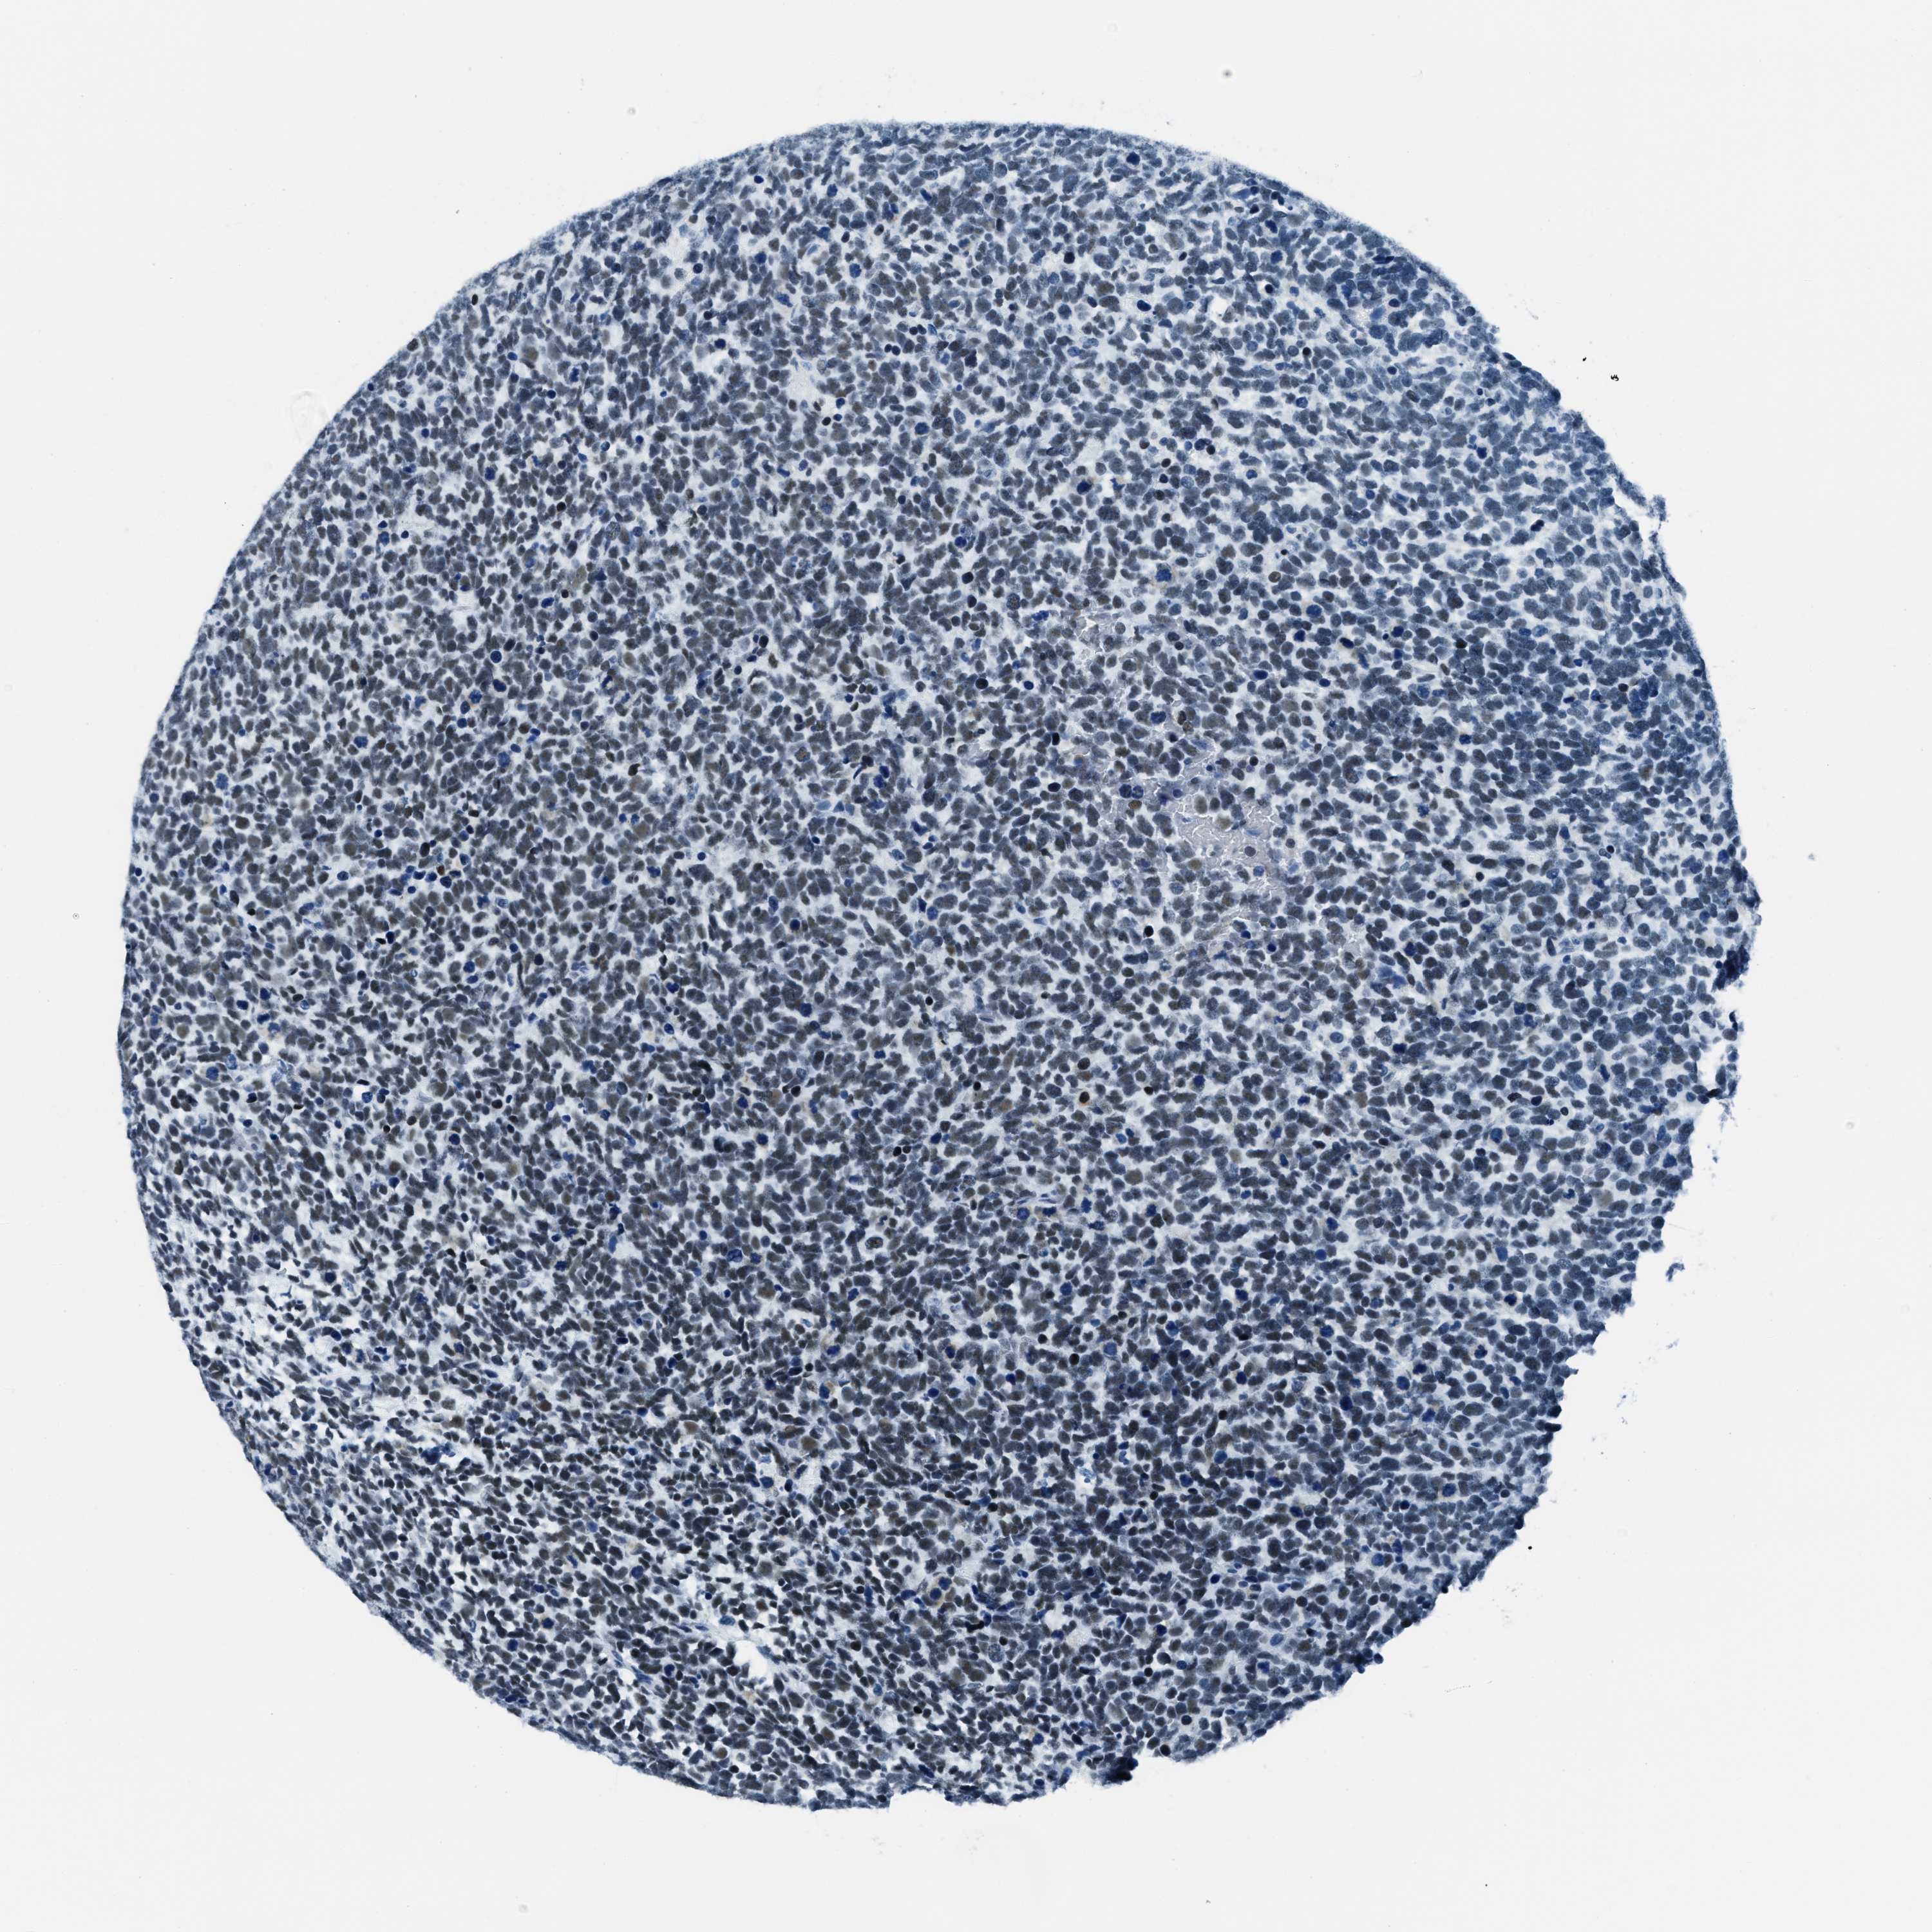

UROTHELIAL CANCER - Protein expressioni

A mouse-over function shows sample information and annotation data. Click on an image to view it in a full screen mode. Samples can be filtered based on level of antibody staining by selecting one or several of the following categories: high, medium, low and not detected. The assay and annotation is described here.

Note that samples used for immunohistochemistry by the Human Protein Atlas do not correspond to samples in the TCGA dataset.

Antibody stainingi

Antibody staining in the annotated cell types in the current human tissue is reported as not detected, low, medium, or high, based on conventional immunohistochemistry profiling in selected tissues. This score is based on the combination of the staining intensity and fraction of stained cells.

Each image is clickable and will lead to virtual microscopy that enables deeper exploration of all samples and also displays staining intensity scores, fraction scores and subcellular localization as well as patient and tissue information for each sample.

Antibody HPA015236

Staining

High

Medium

Low

Not detected

Intensity

Strong

Moderate

Weak

Negative

Quantity

>75%

75%-25%

<25%

None

Location

Urothelial carcinoma, Low grade

Urothelial carcinoma, High grade